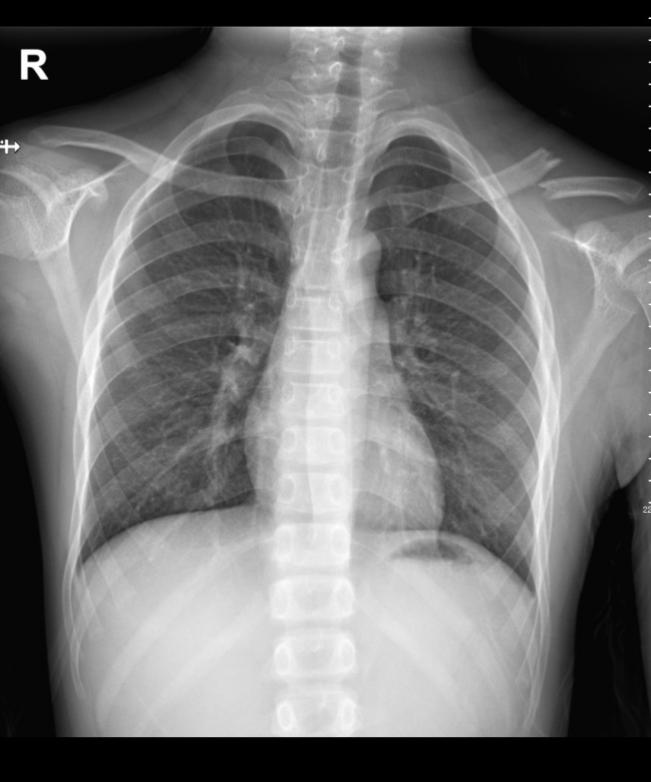

1. X线摄影:也就是我们日常所说的拍片,是最基础的放射检查方法。它操作简便、检查速度快、费用相对较低,常用于检查骨骼系统疾病,如骨折、骨肿瘤等。当我们不小心摔倒怀疑骨折时,拍一张X线片,就能清楚地看到骨头是否断裂以及断裂的位置和程度。在胸部检查方面,X线胸片可以帮助医生发现肺部的一些明显病变,如肺炎、肺结核、肺部肿瘤等,但对于一些早期或较小的病变,可能容易漏诊。

正常胸片和左锁骨骨折